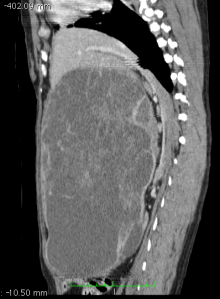

Splenectomy in the dog

Buster the Dog's Massive Spleen Splenectomy in the dog is commonly performed in general practice but I thought that ...